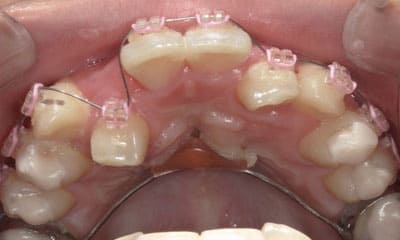

● 先天性の萌出方向異常を部分矯正で治療

藤沢デンタルオフィスの虫歯や破折で先天性の萌出方向異常を部分矯正で治療

04

05

06